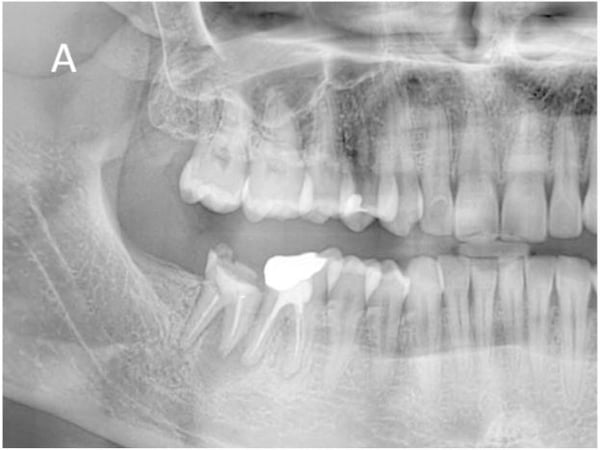

This case involved a 70-year old male who presented with a failing bridge in the lower right posterior quadrant.